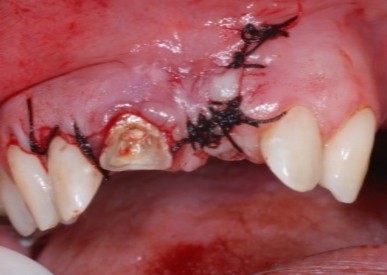

Por fim o retalho foi reposicionado e, então suturado. Foram prescritos um comprimido de sies em seis horas, por dois dias, de paracetamol 750mg. Em sete dias a sutura foi removida, e o paciente relatou um pós-operatório sem complicações.

Devido à persistência do exsudato via canal, optou-se pela realização da obturação endodôntica, seguida de tratamento cirúrgico complementar (apicectomia) com retrobturação com MTA.

- Figura 17 – Sutura com fio de seda 4.0.